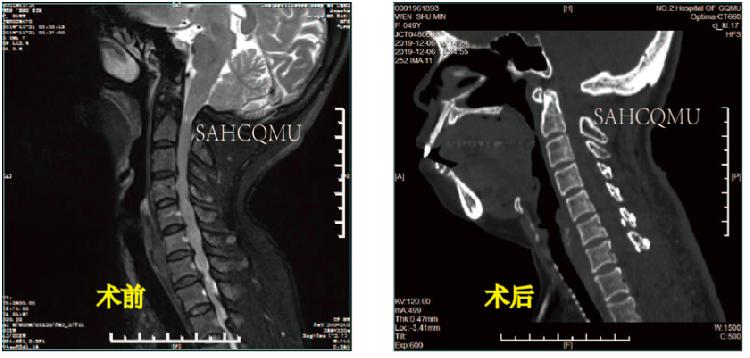

(C1后弓切除+颈椎后路单开门+T1、T2椎板切除减压术·术前术后对比)

但如果遇到:颈椎病变的节段太多、太高;广泛的颈椎后纵韧带骨化症;黄韧带肥厚、骨化、椎板增生肥厚等;下颈椎骨折脱位如合并单、双侧关节突交锁等情况是,前路手术困难且减压不彻底,我们会采取后路手术。汪洋介绍,颈椎后路开门手术就是将脊髓后面的椎板和韧带从上到下,从一侧或两侧翻开,扩大脊髓后方的空间, “来自前方的压迫虽然还在,但是脊髓可以向后躲避,这样一来压迫也就解除了。”